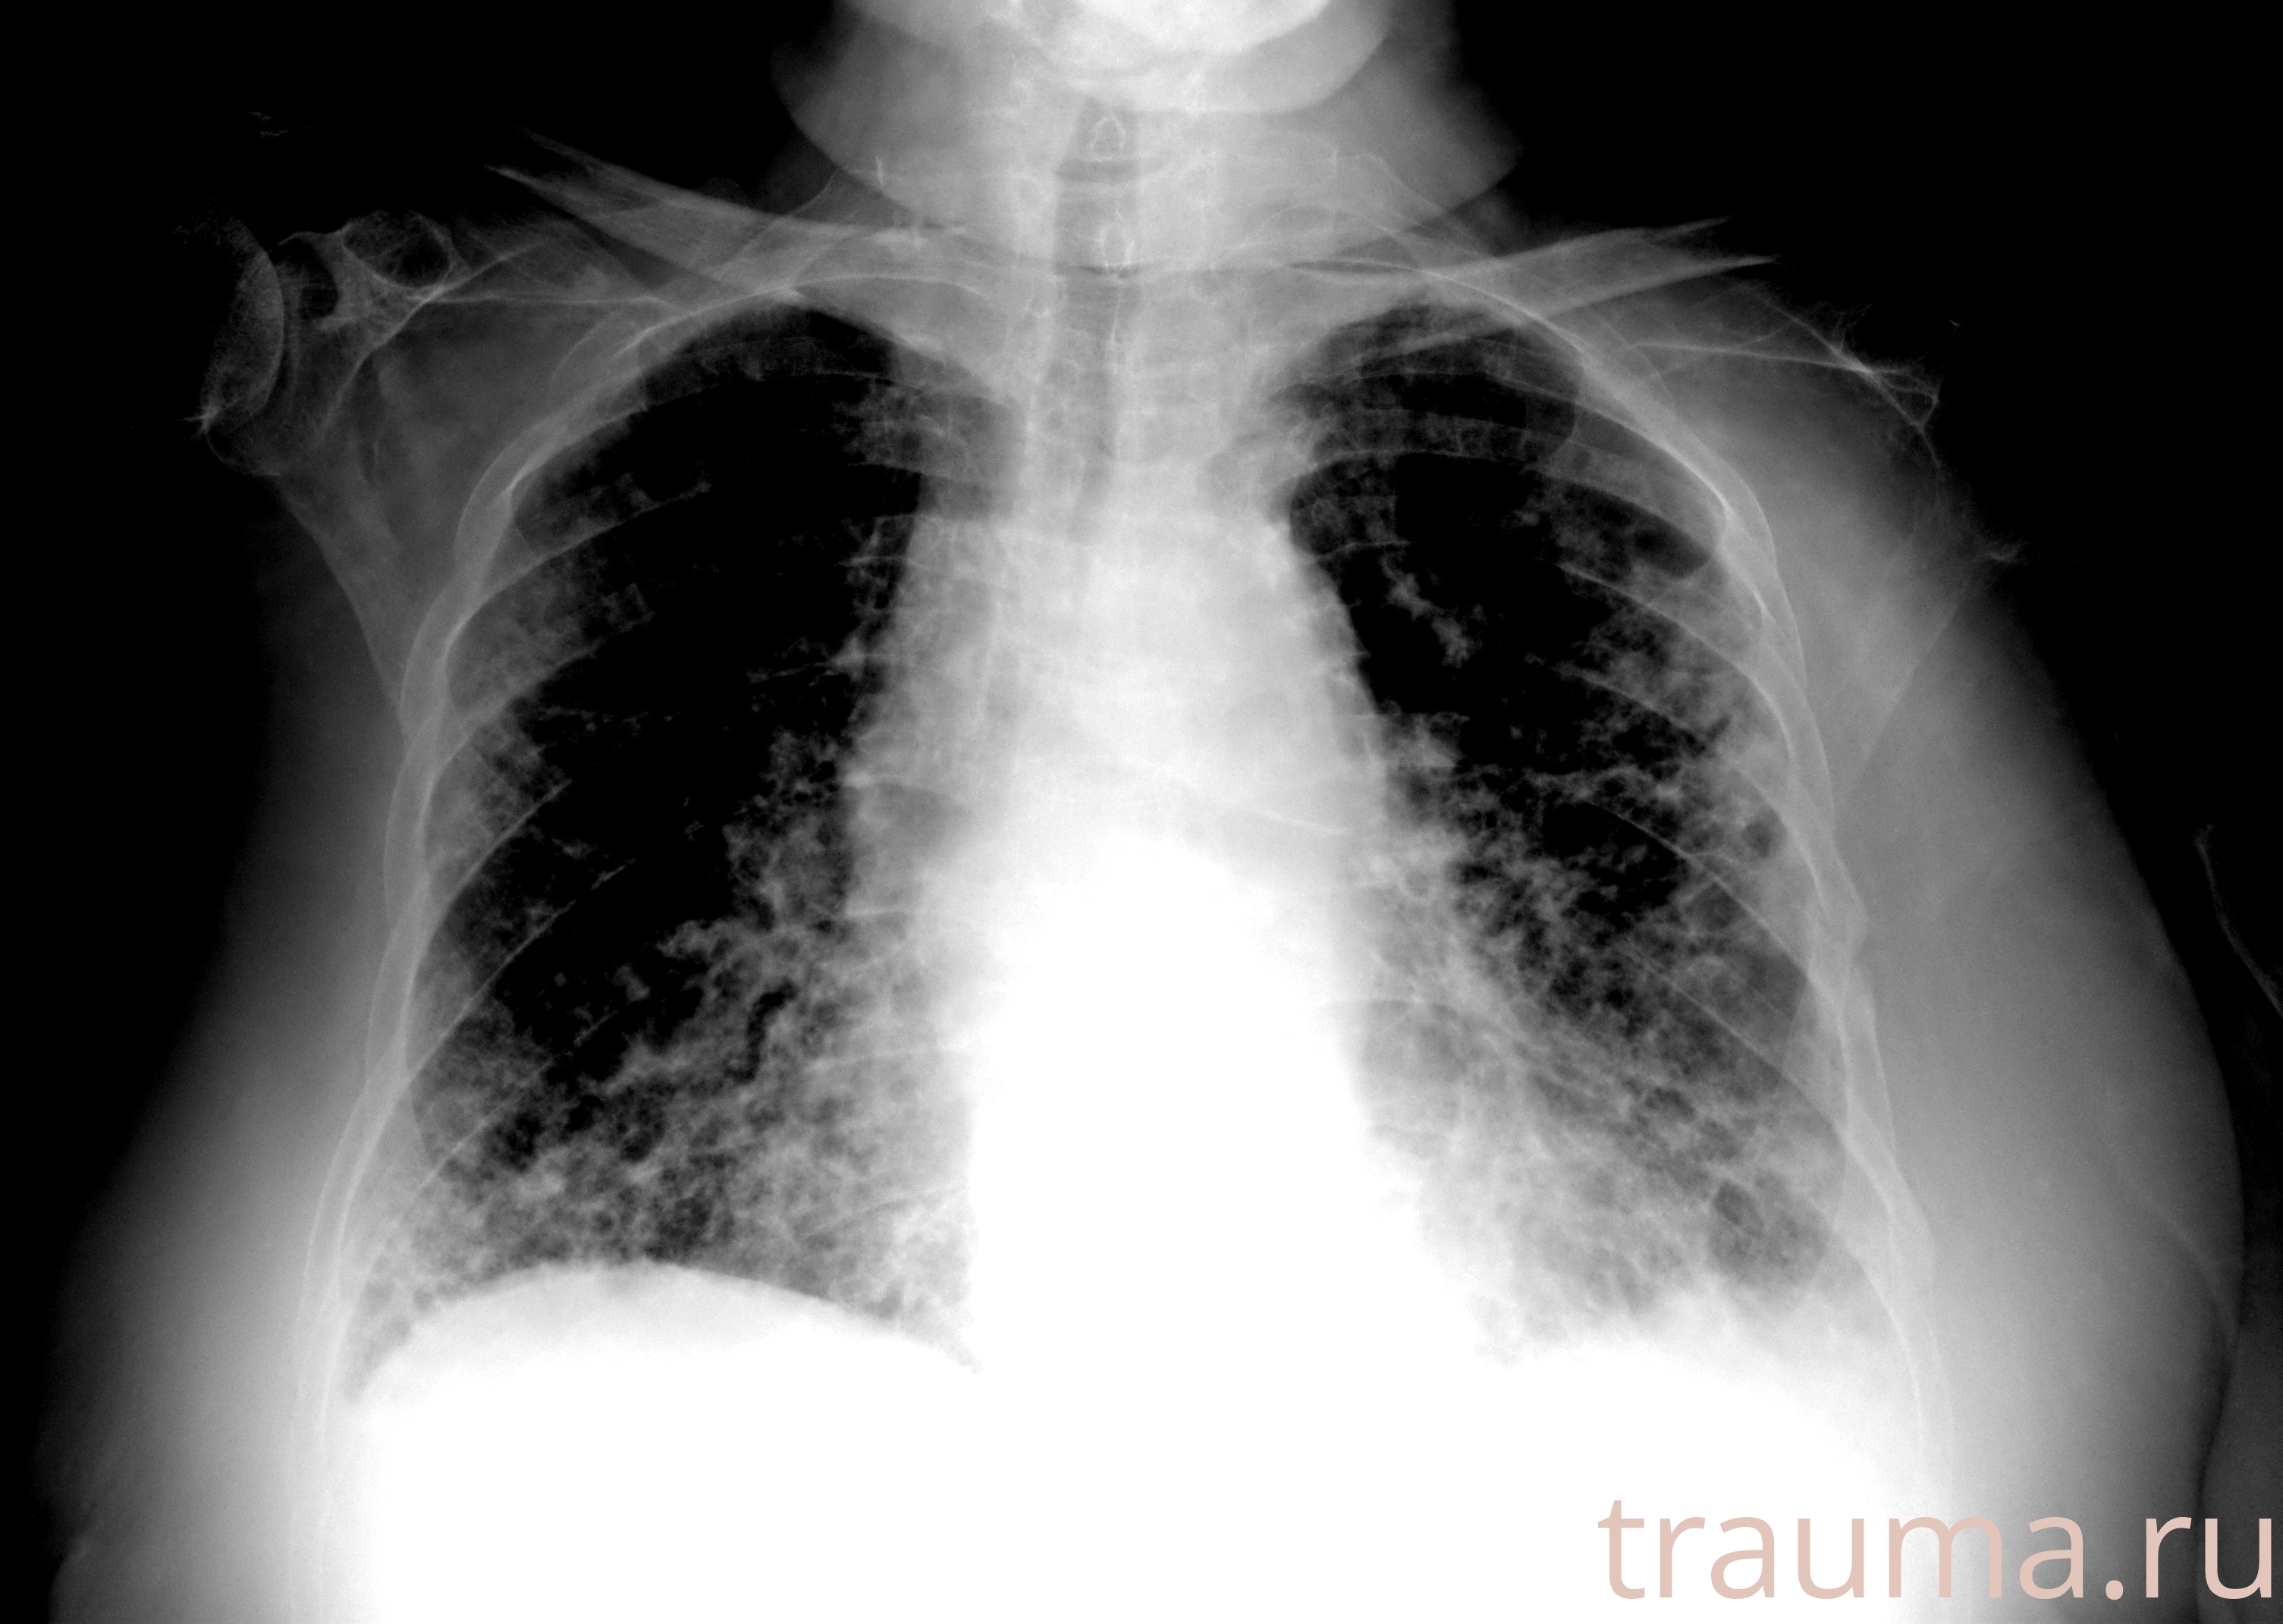

Рентгенограммы

Рентген на дому: по вашему адресу приезжает врач-рентгенолог, травматолог-ортопед с мобильным рентгеновским аппаратом, проводит диагностику травмы или заболевания, делает необходимые рентгенограммы, дает рекомендации по дальнейшему лечению. Получить качественные снимки в домашних условиях возможно благодаря уникальной методике, разработанной МосРентген Центром для института  Склифосовского

при переломе шейки бедра и пневмонии от компании МосРентген Центр - партнера Института имени Склифосовского